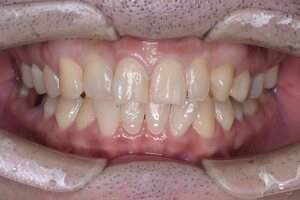

症例① セラミックインレー

治療前

治療後

年齢 60代女性

主訴 歯がしみる

治療方針 つめ物がすでに入っている歯です。そのため、見た目では虫歯があるかどうかわかりませんでしたので、レントゲンを撮影しました。すると、つめ物の中で虫歯になっていることがわかりました。虫歯は、とても大きくなっており神経に近い部分まで進行していました。

治療内容 神経が保存できるかどうか経過をみるために、覆罩といって、神経を守るための処置を行いました。2ヶ月ほど経過を見て、症状が出ないことを確認して、つめ物の型をとり、つめ物をいれていきました。

治療期間 3ヶ月

リスク・副作用 治療後に冷たいものがしみるなどの症状がでることがあります。つめ物を入れた後に痛みなどの症状が出てしまう場合は神経を取り除く治療が必要になります。

費用 ・セラミックインレー:55,000円(税込)

見た目では全くわかりませんが、レントゲンでは黒く抜けて虫歯になっていることがわかります。

虫歯の見分け方